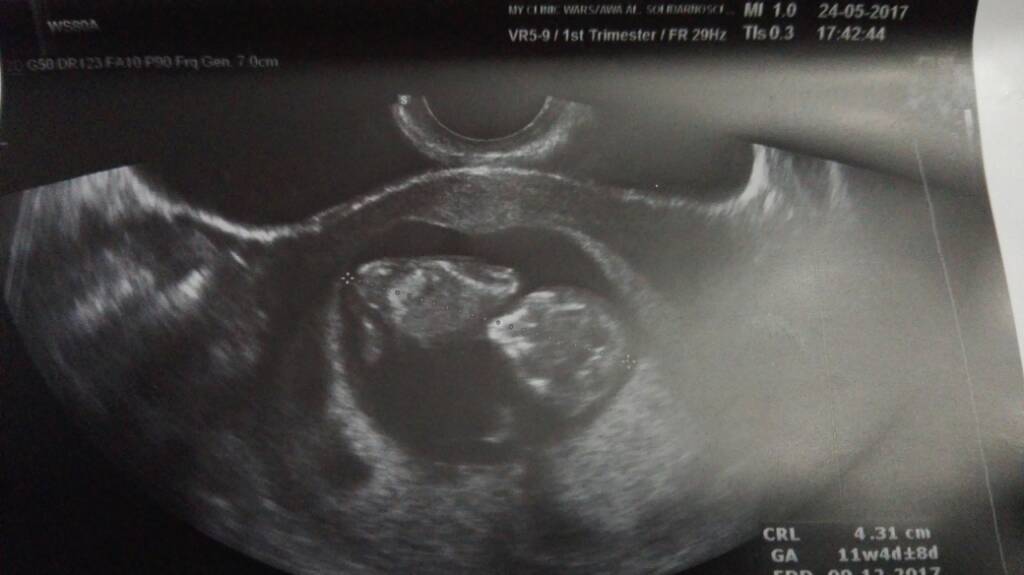

Mam, mam. Co prawda nie 3d ale i tak śliczne ;)

1495650321-aaaaaa.jpeg

Dzidziuś ma 5.5cm

Przeziernosc 1.1mm czyli w porządku uff!!!

Serduszko pięknie bije 168.

Kosmowka się zespolila i już idzie do góry. Doktor pozwolił mi chodzic po podwórku jupi :-D płeć 50/50 więc nie wiem nic Haha.